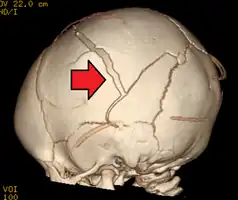

A skull fracture from abusive head trauma in an infant -

3D CT reconstruction showing a skull fracture in an infant -

3D CT reconstruction showing a skull fracture in an infant

AHT may be misdiagnosed, underdiagnosed, and overdiagnosed,[26] and caregivers may lie or be unaware of the mechanism of injury.[11] Commonly, there are no externally visible signs of the condition.[11] Examination by an experienced ophthalmologist is often critical in diagnosing shaken baby syndrome, as particular forms of ocular bleeding are quite characteristic.[27] Magnetic resonance imaging may also depict retinal bleeding;[28] this may occasionally be useful if an ophthalmologist examination is delayed or unavailable. Conditions that are often excluded by clinicians include hydrocephalus, sudden infant death syndrome (SIDS), seizure disorders, and infectious or congenital diseases like meningitis and metabolic disorders.[29][30] CT scanning and magnetic resonance imaging are used to diagnose the condition.[11] Conditions that may accompany AHT include bone fractures, injury to the cervical spine (in the neck), retinal bleeding, cerebral bleed or atrophy, hydrocephalus, and papilledema (swelling of the optic disc).[12]